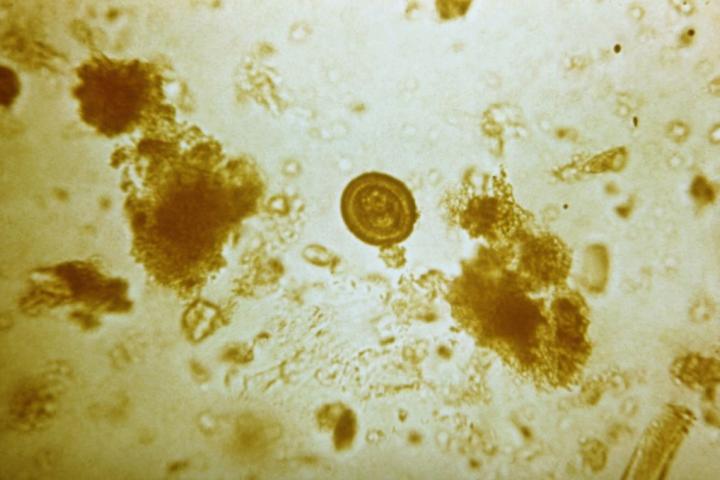

Una radiografía que da miedo. El doctor norteamericano Sam Ghali compartió el pasado 16 de enero en sus redes sociales la impresionante imagen de la pelvis de un hombre que tenía cientos de huevos de un parásito plano que habita en el intestino humano. "Es una de las radiografías más locas que he visto en mi vida", ha señalado el médico.

Las impactantes imágenes mostraban una enfermedad parasitaria llamada cisticercosis. Dicha dolencia es causada por la ingestión de huevos de la T solium. Estos se encuentran en los alimentos contaminados. La autoinfección se presenta cuando una persona ya infectada con T solium adulto ingiere luego los huevos. Esto ocurre por no lavarse bien las manos después de una deposición (transmisión fecal-oral).